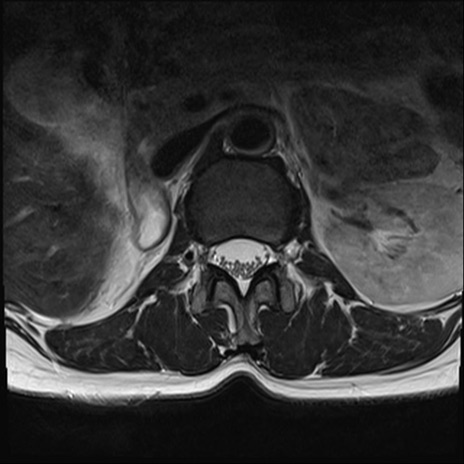

【整形】TIPS症例4 腰椎MRI T2WI(横断像)

腰椎MRI

横断像と矢状断像